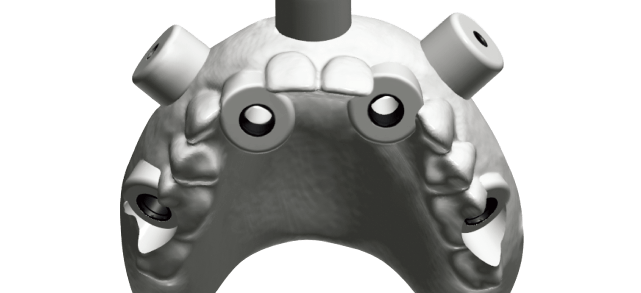

Diagnostic Wax Up Surgical Guide

Surgical Guide Surgical Guide Planning

Surgical Guide Planning

-Implant CT Surgical Guide